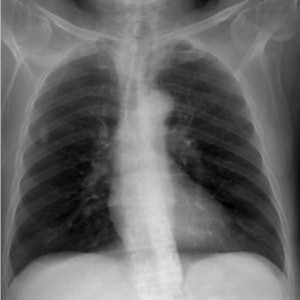

Top: Digitally reconstructed radiograph (DRR) of a chest x-ray reconstructed with a tube potential of 50 kVp. Below: DRR of a chest x-ray reconstructed with a tube potential of 150 kVp. Bottom: DRR of a chest x-ray reconstructed with an antiscatter grid. There is increased detail in the spine and diaphragm region. All images courtesy of Craig Moore.

The model was validated with a phantom and patients; it provided predictions of signal-to-noise ratios, tissue-to-rib ratios, and pixel value histograms that lie within the range of values measured with patients and the phantom. The maximum difference in measured signal-to-noise ratios to that calculated was 10%. Tissue-to-rib ratio values differed by a maximum of 1.3%.

They found anatomical noise was adequately simulated using human chest CT datasets. Scatter and system noise was successfully added post-DRR calculation, which resulted in signal-to-noise ratios, tissue-to-rib ratios, and pixel value histograms that are in good agreement with those measured in CR-acquired images.

"Although DRR resolution is not as good as real CR images, four independent expert image evaluators believe DRR images adequately simulate real radiographs and provide realistic anatomical features. Therefore, this computer model provides us with a tool that can be used by radiologists to grade quality for images derived with different x-ray system parameters, without the need to perform repeat exposures on patients," they wrote.